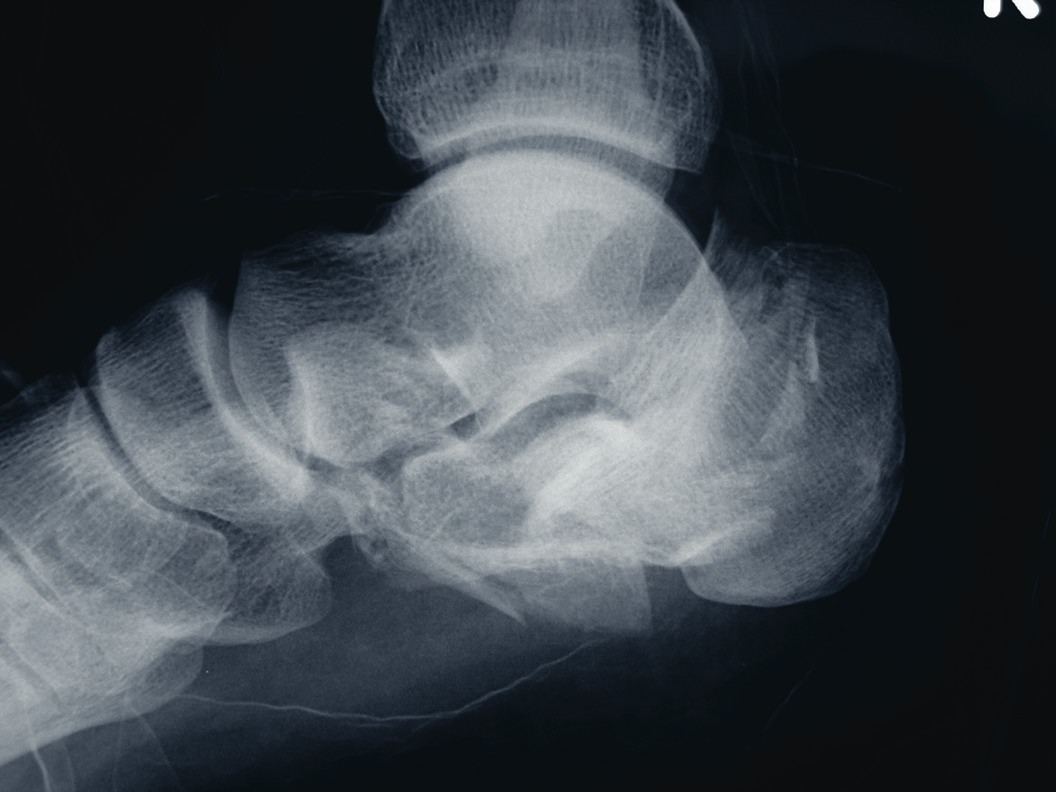

Below The Ankle Frame: A New Option For Calcaneal Fractures?

By Brian McCurdy, Senior Editor Can a below the ankle circular Ilizarov frame adequately treat displaced calcaneal fractures? A recent study in the Journal of Foot and Ankle Surgery examines the effects of the new type of frame. Study authors say combining these frames with minimally invasive fragment reduction techniques may help reduce and stabilize calcaneal fractures. In the study, authors note that their proposed frame is lightweight and its two rings are confined to the foot. They have thus far treated 19 patients with the below-the-ankle frame and claim the frames achieved and maintained reduction in all patients except one. They note a satisfactory early clinical outcome and say no patients exhibited restriction of ankle joint movement. The ring mount hangs from a 5/8 reference ring at the level of the talus, notes the study. The authors say three olive wires through the talus and midfoot improve stability of the reference ring. A foot plate attached to the tuberosity with two wires serves as a reduction platform. As the authors point out, placing the rings parallel will correct gross displacement. The study says an olive wire attached to the reference ring holds the reduced articular surface. Gary Jolly, DPM, says “there may be some real value to not involving the ankle in the construct and allowing it to move during the patient’s convalescence.” However, Dr. Jolly cautions that podiatric surgeons can only use such frames in states where the scope of practice limits conventional frame usage. He also notes that bench top testing is needed in order to clarify the sturdiness of the below ankle frame. “While traditional frames may be walked on, those which do not include the lower leg have no scientific validity,” says Dr. Jolly, a Fellow and Past President of the American College of Foot and Ankle Surgeons.